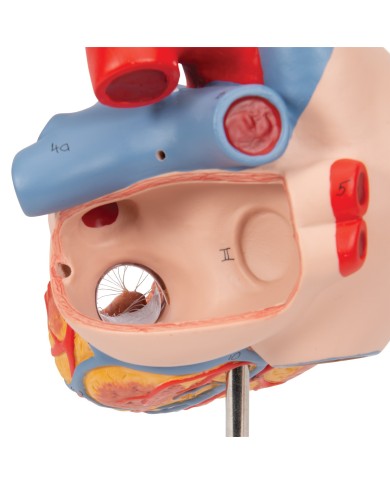

Modello di cuore di alta qualità scomponibile in 5 parti

Modello di cuore di alta qualità scomponibile in 5 parti

La parete anteriore del cuore è staccabile per poter vedere i ventricoli.